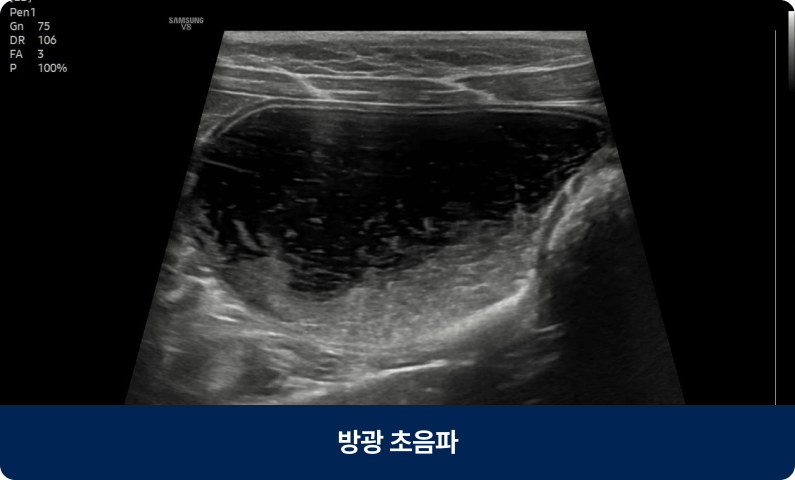

신장센터는 신장의 여과 기능 이상과 요로계 질환을 진단·치료하는 분야입니다. 아프리카 동물의료센터는 신장 전문 의료진이 정밀 검사를 통해 장기 기능을 보호하는 맞춤형 치료 계획을 제공합니다.

신장센터는 신장의 여과 기능 이상과 요로계 질환을 진단·치료하는 분야입니다.

아프리카 동물의료센터는 신장 전문 의료진이 정밀 검사를 통해 장기 기능을 보호하는 맞춤형 치료 계획을 제공합니다.